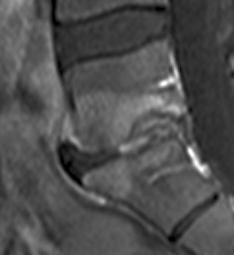

Discopathie L4-L5 MODIC 2